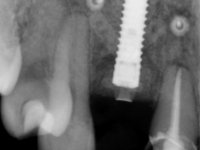

Paciente do sexo feminino, com 36 anos de idade, não fumadora. Apresentava o dente 1.1 com uma tonalidade mais escura que os dentes adjacentes. Feito o exame imagiológico, observou-se que o dente 1.1 tinha tratamento endodôntico, a paciente tinha 3 implantes colocados, dois no local dos dentes 1.2 e 2.2 e o outro no 4.6. A paciente tinha sido tratada ortodonticamente, apresentava um fenótipo gengival médio e uma boa higiene oral. Após 5 anos da primeira intervenção a paciente apresenta-se na consulta com sintomatologia infeciosa compatível com uma peri-implantite nos implantes 1.2 e 4.6. Após exame clínico, foi confirmada imagiológicamente. A perda óssea vertical tinha mais de 4mm nas duas situações.

Após 5 anos da primeira intervenção, a paciente surge na consulta com uma peri-implantite nos implantes colocados no local dos dentes 1.2 e 4.6. Começamos por abordar a peri-implantite no local do dente 2.2. Foi feita uma ponte provisória de laboratório em acrílico com 2 elementos. O dente 1.1 como pilar e o 1.2 como pôntico, este último apresentava um apoio distal. A coroa do 1.2 foi removida do coto com um corte longitudinal feito com turbina e depois foi fraturada com um mini luxador. O coto foi de seguida desaparafusado do implante. Fez-se o mesmo procedimento para remover a coroa do 1.1. O dente 1.1 foi re-preparado e a ponte provisória foi rebaseada em boca com acrílico autopolimerizável. Feito o correto acabamento e polimento da provisória foi feita a sua cimentação temporária com cimento de policarboxylato. Numa consulta posterior. foi feita a remoção da ponte provisória, feita a cirurgia para explantação do implante, colocou-se um novo implante e fez-se a regeneração óssea da zona com uma membrana não reabsorvível. 3 meses após foi removida a coroa do implante colocado no 4.6. Foi feito um corte horizontal com turbina na zona cervical e com um mini luxador descolou-se a coroa do coto. Após este procedimento fez-se a explantação do implante. Após 6 meses foi colocado um novo implante no local do 4.6. Após a osteointegração foi feita a impressão com a técnica de moldeira aberta e foi confecionada em laboratório uma coroa aparafusada sobre o implante. Aprovada pela paciente foi apertada definitivamente em boca. Após 1 mês removemos a ponte provisória antero-superior, reforçamos o dente 1.1 com um poste intra- radicular e reconstruimos o coto com uma resina de polimerização dual. Nessa mesma consulta expomos o implante colocado no 1.2 e fizemos uma impressão pela técnica de moldeira aberta com silicone de dupla viscosidade e presa rápida. No laboratório foi feita uma ponte provisória de 2 elementos, aparafusada sobre o implante e cimentada sobre o dente. A primeira ponte provisória foi removida e colocada a segunda aparafusada sobre o implante. A linha de acabamento cervical do 1.1 foi rebaseada com resina composta durante o aperto do parafuso do implante. Depois foi removida, foram feitos os acabamentos e finalmente apertada sobre o implante e cimentada temporariamente sobre o dente. Após 2 meses de maturação dos tecidos moles em função do perfil de emergência criado pela nova ponte provisória, pudemos avaliar a estética conseguida em conjunto com a paciente. Neste longo processo o dente 2.1 teve que fazer um tratamento endodôntico. Decidiu-se assim fazer também uma coroa no dente 2.1.O dente 2.1 foi preparado na mesma consulta em que se fez a impressão ao implante. A ponte provisória foi utilizada para individualizar a peça de transferência, copiando o seu perfil de emergência e em seguida foi realizado o afastamento gengival com caolino. A impressão foi feita com a técnica de moldeira aberta com silicone de dupla viscosidade e presa rápida. Após a escolha da cor, a impressão foi enviada  para o laboratório onde foram confecionadas 2 coroas  com infraestrutura em Zr. revestidas a cerâmica para os dentes 1.1 e 2.1 e uma coroa aparafusada sobre o implante no dente 1.2. O trabalho final foi aprovado pela paciente e foi colocado definitivamente em boca. A coroa sobre o implante foi aparafusada com 35 N e as coroas foram cimentadas com cimento de ionómero de vidro reforçado com resina.